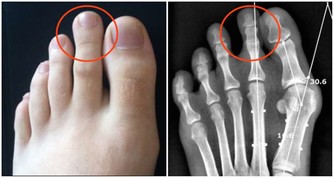

三、按壓太沖穴:排肝毒消火氣

太沖穴為肝經的原穴,可以調理肝的疏泄氣機機能,具備補虛瀉實的雙重作用,

還能激發肝經氣血、清肝利膽,從而起到補肝的效果。

取穴位置

腳背大拇趾和第二個腳趾,夾縫向上的凹陷處。

按壓太沖穴手法

1、按摩此穴時,最好先用溫水浸泡雙腳10~15分鐘,以舒活足部的氣血。

2、用拇指按揉太沖穴3—5分鐘,感覺輕微酸脹為佳,兩隻腳交替按壓。